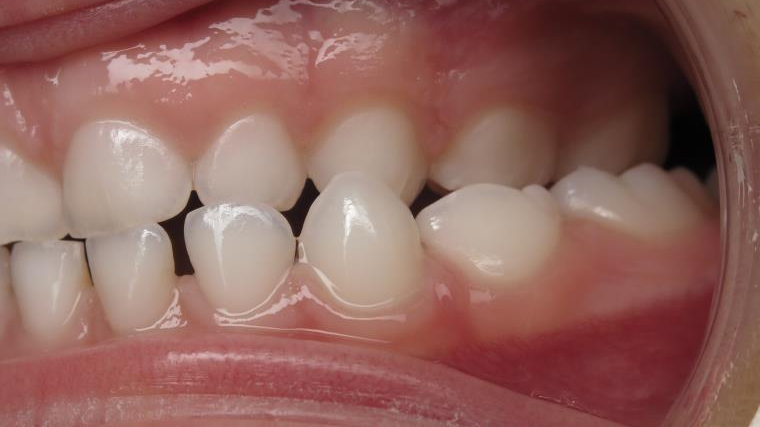

25. bout à bout anterieur 6 ans

dents du haut bout à bout par rapport à celle du bas